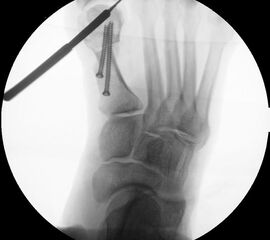

Abbildung 1

• Korrekturpotential größer als beim offenen Chevron, da die Gelenkkapsel als stabilisierendes Element erhalten bleibt und über eine trikortikale Osteosynthese mit zwei kanülierten Schrauben eine Verschiebung bis ca. 80% des Metatarsaledurchmessers möglich ist (Abb. 1).